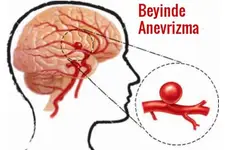

Beyin Dokusunun Sağlık Üzerindeki Etkileri Beyin dokusunun sağlıklı bir şekilde işlev görmesi, genel sağlık üzerinde büyük etkiye sahiptir. Beyin dokusundaki hasar veya bozulmalar, birçok nörolojik hastalığın temelini oluşturur. Öne çıkan sağlık sorunları arasında: